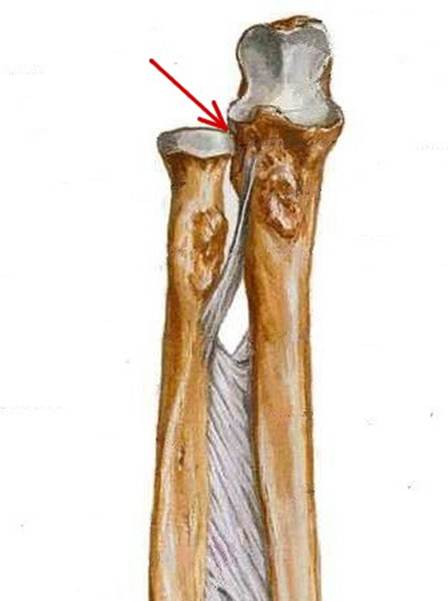

S: Стрелкауказывает на суставная окружность (circumferentia art.)

S: Стрелкауказывает на tuberositas radii (бугристость)

S: Стрелкауказывает на collum radii (шейка)

S: Стрелка указывает на lig. Anulare radii

S: Стрелка указывает на tuberositas radii

S: Стрелка указывает на articulation radii